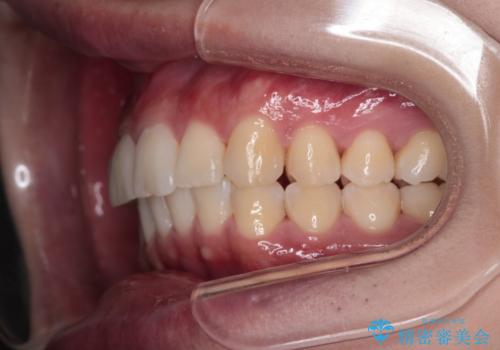

【インビザライン】短期間で出っ歯を治したい

- 出っ歯と口元の突出感が気になるということで来院されました。抜歯矯正も考えられますが、今回は早く終わらせたいという要望があり非抜歯での治療にしました。また遠方から来院されているため、来院回数のおさえられるインビザラインを選択しました。

非抜歯での治療のため、今回はスペース確保のために遠心移動とおもにIPRの処置を取り入れました。